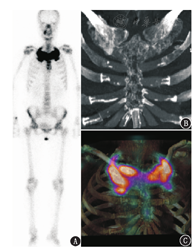

患者女,47岁,因"乳腺癌根治术后3年,左侧胸锁关节疼痛5个月"入院。体格检查:左侧胸锁关节局部肿胀、压痛,局部无皮肤发红。实验室检查:碱性磷酸酶330.2(正常参考值40~150) U/L,血红细胞沉降率41(正常参考值0~20) mm/1 h,余常规检查均阴性。予患者静脉注射99Tcm-MDP(上海欣科医药有限公司苏州分公司提供,标记率>95%)740 MBq后3 h,使用荷兰Philips SPECT/CT(Precedence 16)进行全身前位、后位及胸锁关节区断层采集。全身骨平面显像见两侧胸锁关节区对称性异常浓聚,呈典型的"牛头"征(图1A)。SPECT/CT显示(图1B,图1C)胸骨病变累及胸部柄、胸骨体及剑突,但仅见胸骨切迹周围轻度放射性浓聚,另外两侧第2肋骨与肋软骨连接处亦可见少量放射性浓聚。两侧锁骨、两侧第1肋骨远端膨大;同机CT示锁骨、第1肋骨、胸部及第2肋骨远端骨小梁结构紊乱,呈丝瓜瓤样改变;锁骨与胸骨关节面完整,关节间隙存在,肋锁关节缘亦完整。

核素骨显像是检查SAPHO综合征的灵敏方法,图像上胸锁关节区的对称性浓聚呈典型的"牛头"征,颇具特征性[2,3,4]。SPECT/CT可显示滑膜炎导致的跨关节侵蚀、软骨剥脱及软骨下骨炎等病理改变。原发性或继发性骨肿瘤极少侵蚀关节软骨,不会形成跨关节破坏。本例有皮肤病史、血红细胞沉降率升高,及典型的"牛头"征,类似SAPHO综合征骨显像表现;但累及关节的关节面完整,关节软骨及软骨下骨未见侵蚀破坏和硬化,未见关节间隙肿胀,亦无骨膜反应导致的骨肥厚,不符合关节炎的典型影像表现。本病例表明胸锁关节区"牛头"状浓聚不是SAPHO综合征的独有表现,SPECT/CT有助于诊断和鉴别诊断。